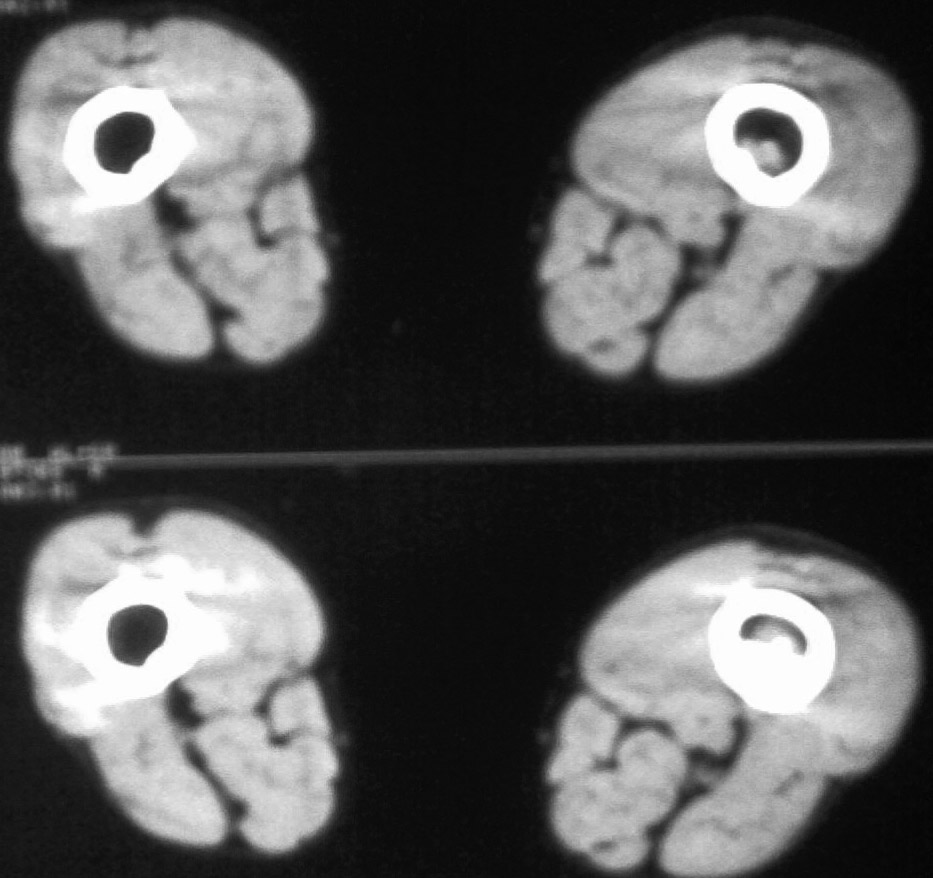

右肱骨中下段恶性肿瘤(纤维肉瘤可能性大)伴病理性骨折。

作者: 随光逐影    时间: 2009-1-28 01:27

支持 右肱骨中下段恶性肿瘤(纤维肉瘤可能性大)伴病理性骨折。

作者: jinguoji    时间: 2009-1-28 02:09

支持 右肱骨中下段恶性肿瘤伴病理性骨折。

右肱骨中下段恶性肿瘤伴病理性骨折

中央型纤维肉瘤主要破坏松质骨,x线表现以局灶性透亮区为主,其中无成骨现象。边缘参差不齐。中间偶可有散在小钙化点,邻近骨皮质局限变薄,轻度膨胀,虽常被穿破,然多无骨膜反应,有些病例,病变范围较广,骨小梁排列紊乱夹杂有骨质破坏的小斑点状透光区,分布弥散,偶有少量骨膜新骨形成。周围型肿瘤常位于软组织中,呈圆形或卵圆形阴影,密度较肌肉影略离,肿块中可出现少量均匀钙化点。